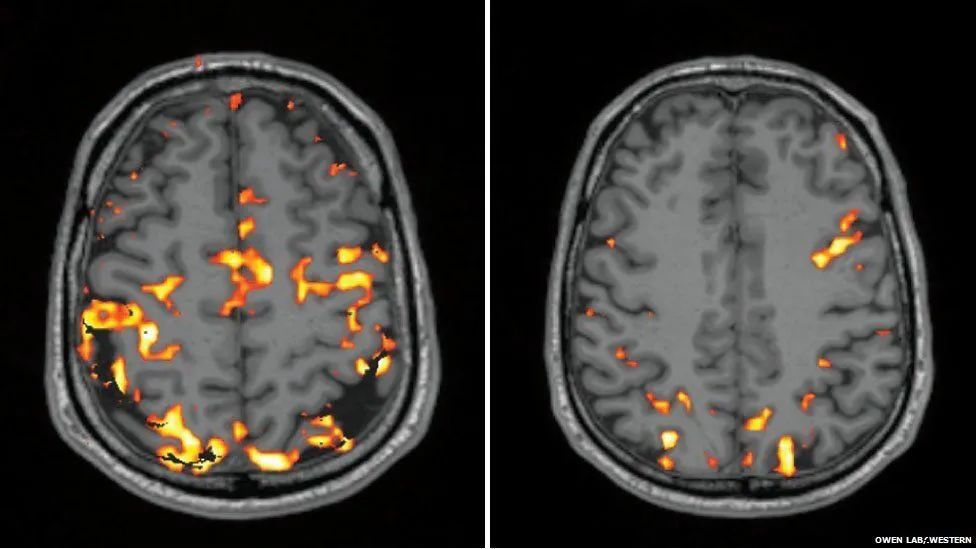

左右分别为正常睡眠和睡眠不足后的大脑活动 | OWEN LAB, WESTERN